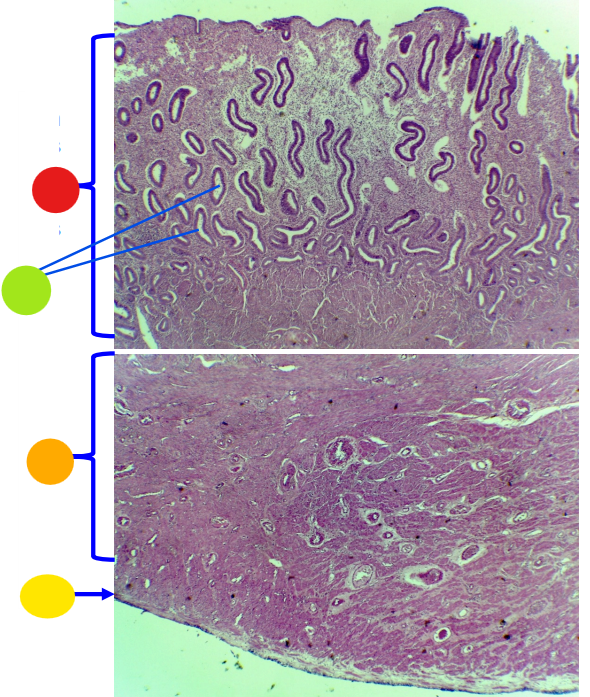

red

tunica albuginea

orange

primordial follicles

red

primary follicle

orange

secondary follicles

what is this

tertiary follicle

What is this

mature follicle

red

cumulus oophorus

orange

tertiary follicle

yellow

intermediate tertiary to mature follicle

red

corpus luteum

orange

tunica albuginea